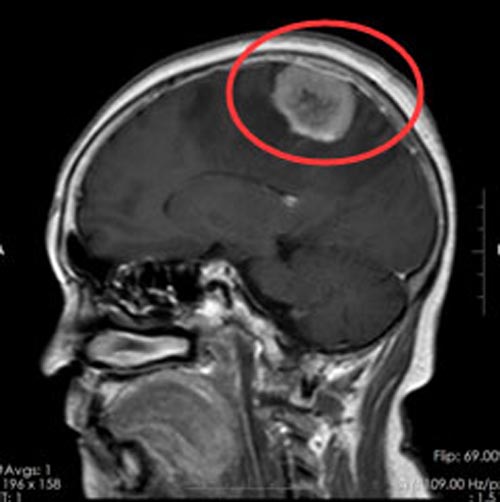

73岁的余阿婆3个月前时常感到头痛头晕,当地医院头颅磁共振检查提示“左侧额部占位,考虑脑膜瘤”,水肿比较明显。家人考虑到她已经年迈,不能承受手术风险,因此选择了保守治疗。但近段时间来,阿婆出现右侧肢体无力,伴有行走不稳,家属思量再三,来到广东三九脑科医院。

取得家属支持后,阿婆在全麻下行“左侧额顶部占位病变切除术”,术中可见肿瘤位于右额顶交界处,大小约3cm×4cm×3cm,将肿瘤全切除,术程顺利。术后的余阿婆恢复良好,肢体活动恢复正常,头痛头晕症状消失。

▲手术前